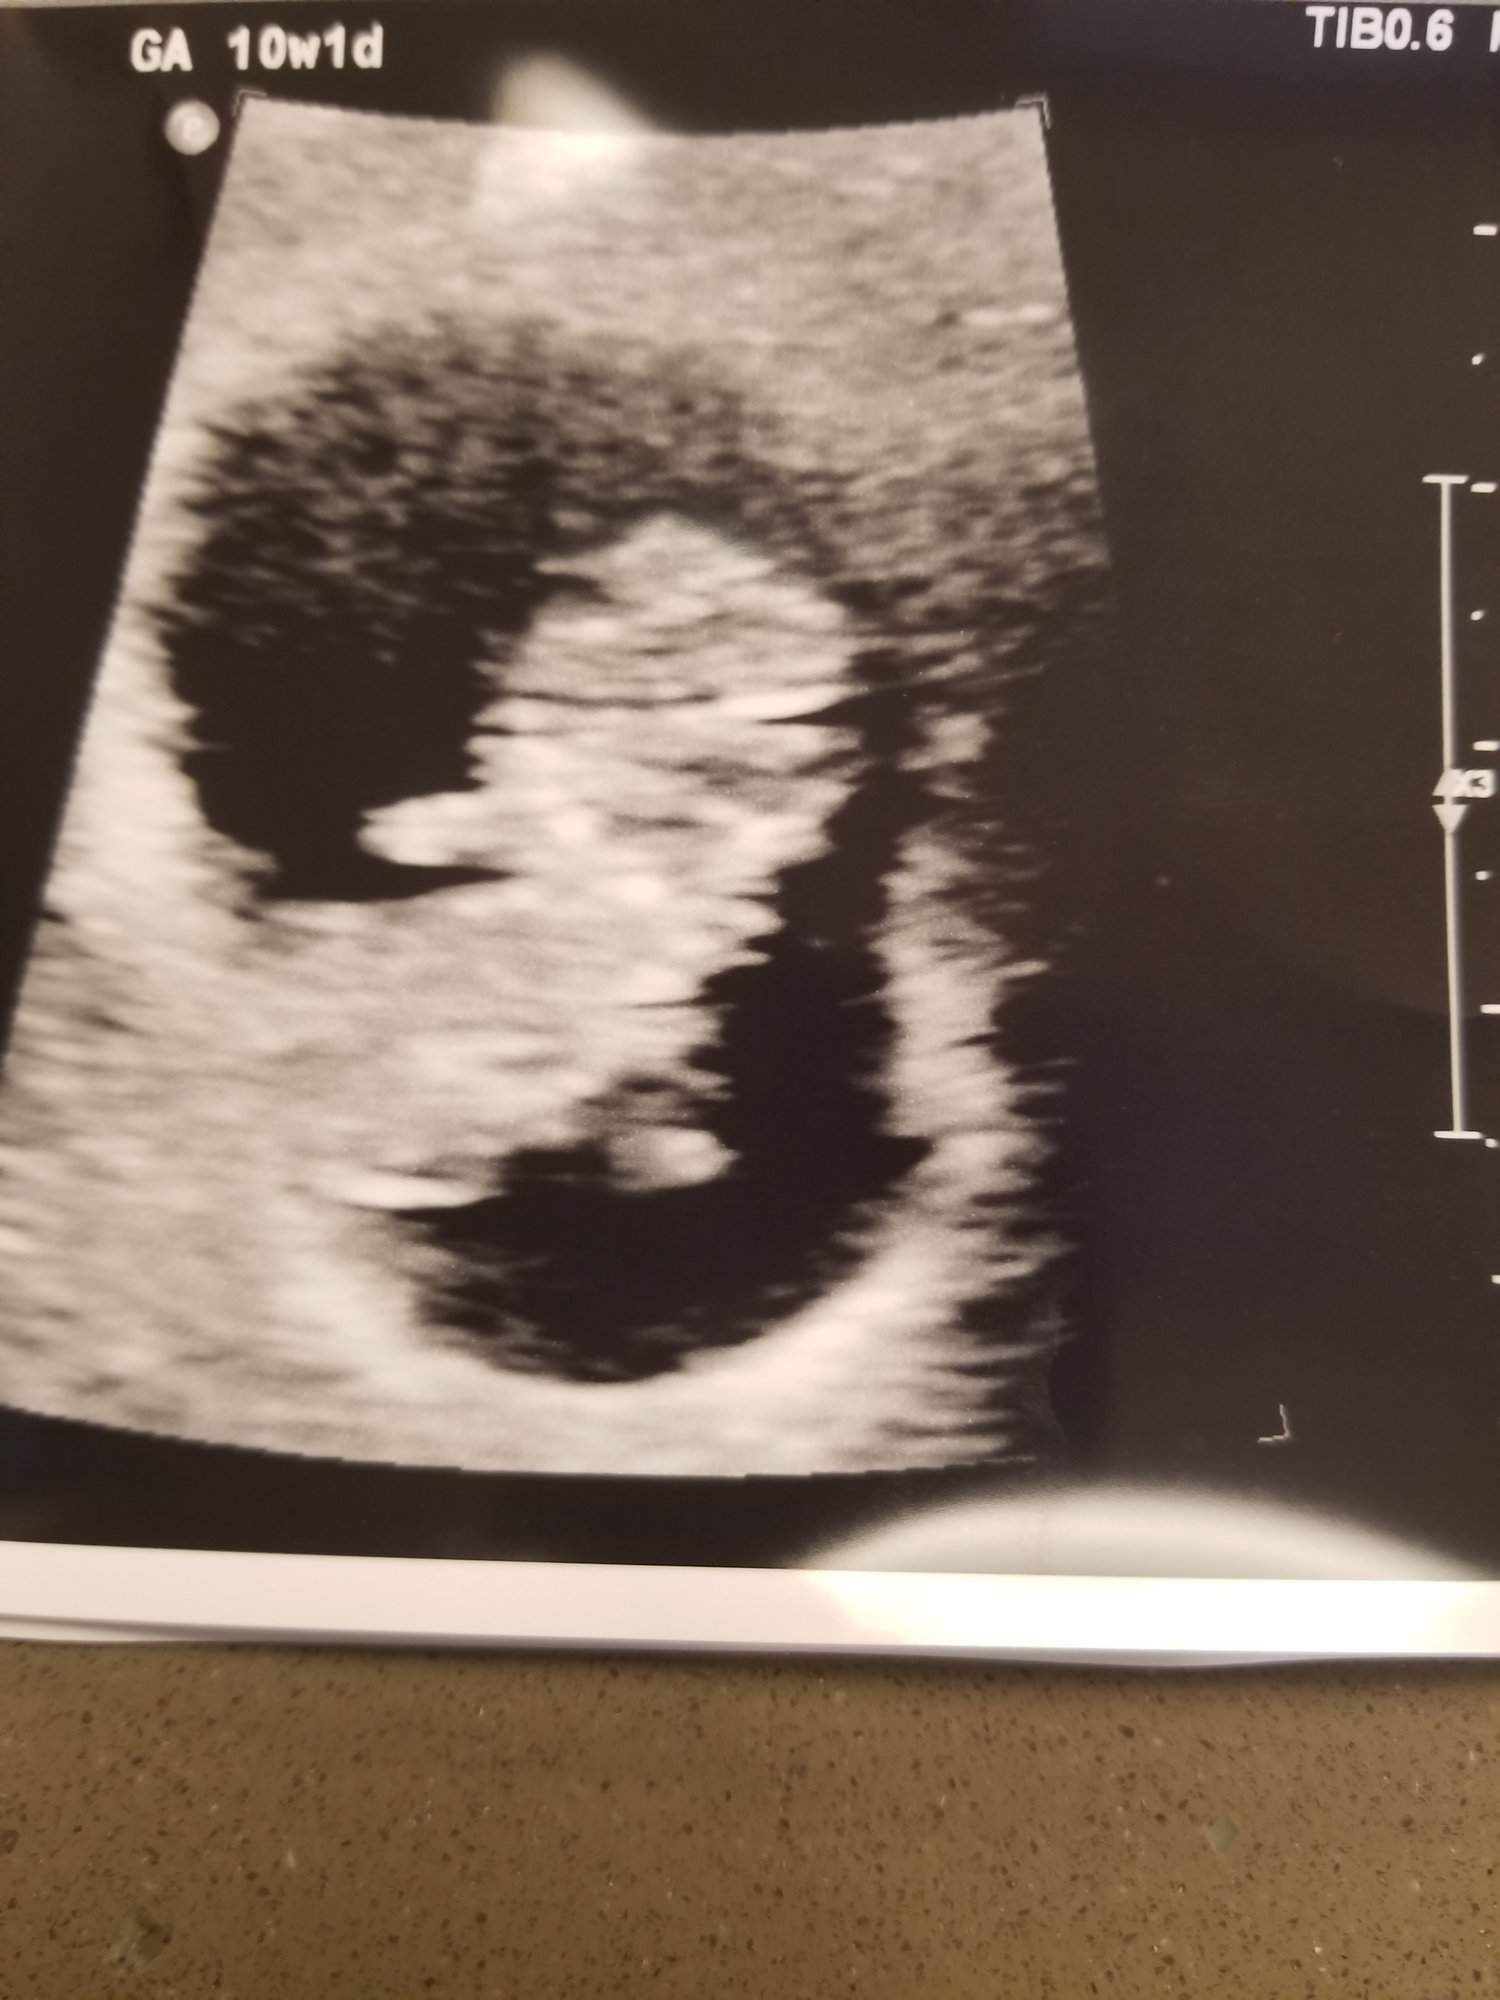

It’s a nugget! Measuring 9w4d, heartbeat of 175. 😍😍😍